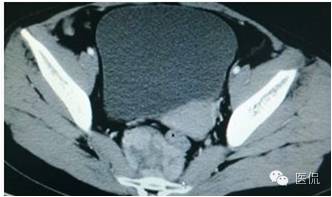

增强动脉期(CT值31HU)